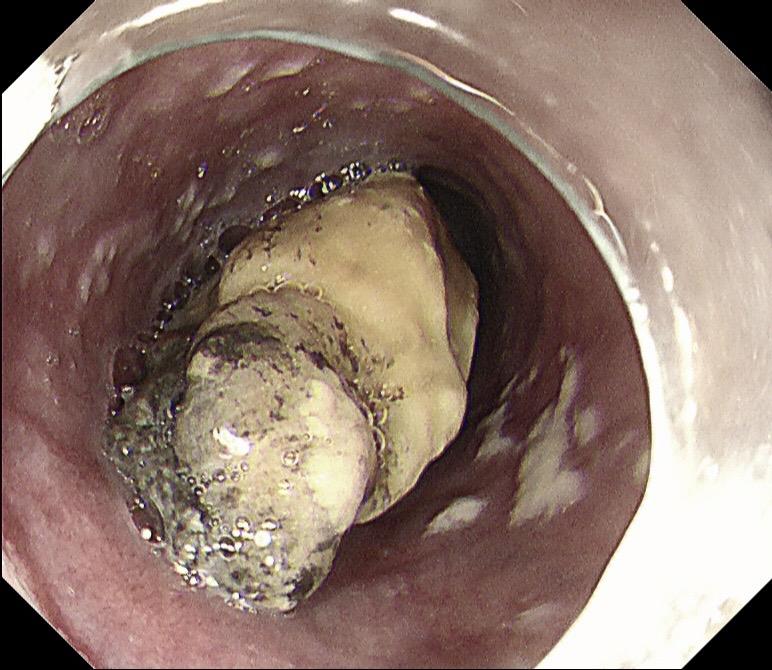

老年人吞咽不畅必有妖!老年人被鲍鱼卡住,做胃镜之前就怀疑是不好的病,胃镜把鲍鱼取出来后一看果然是!